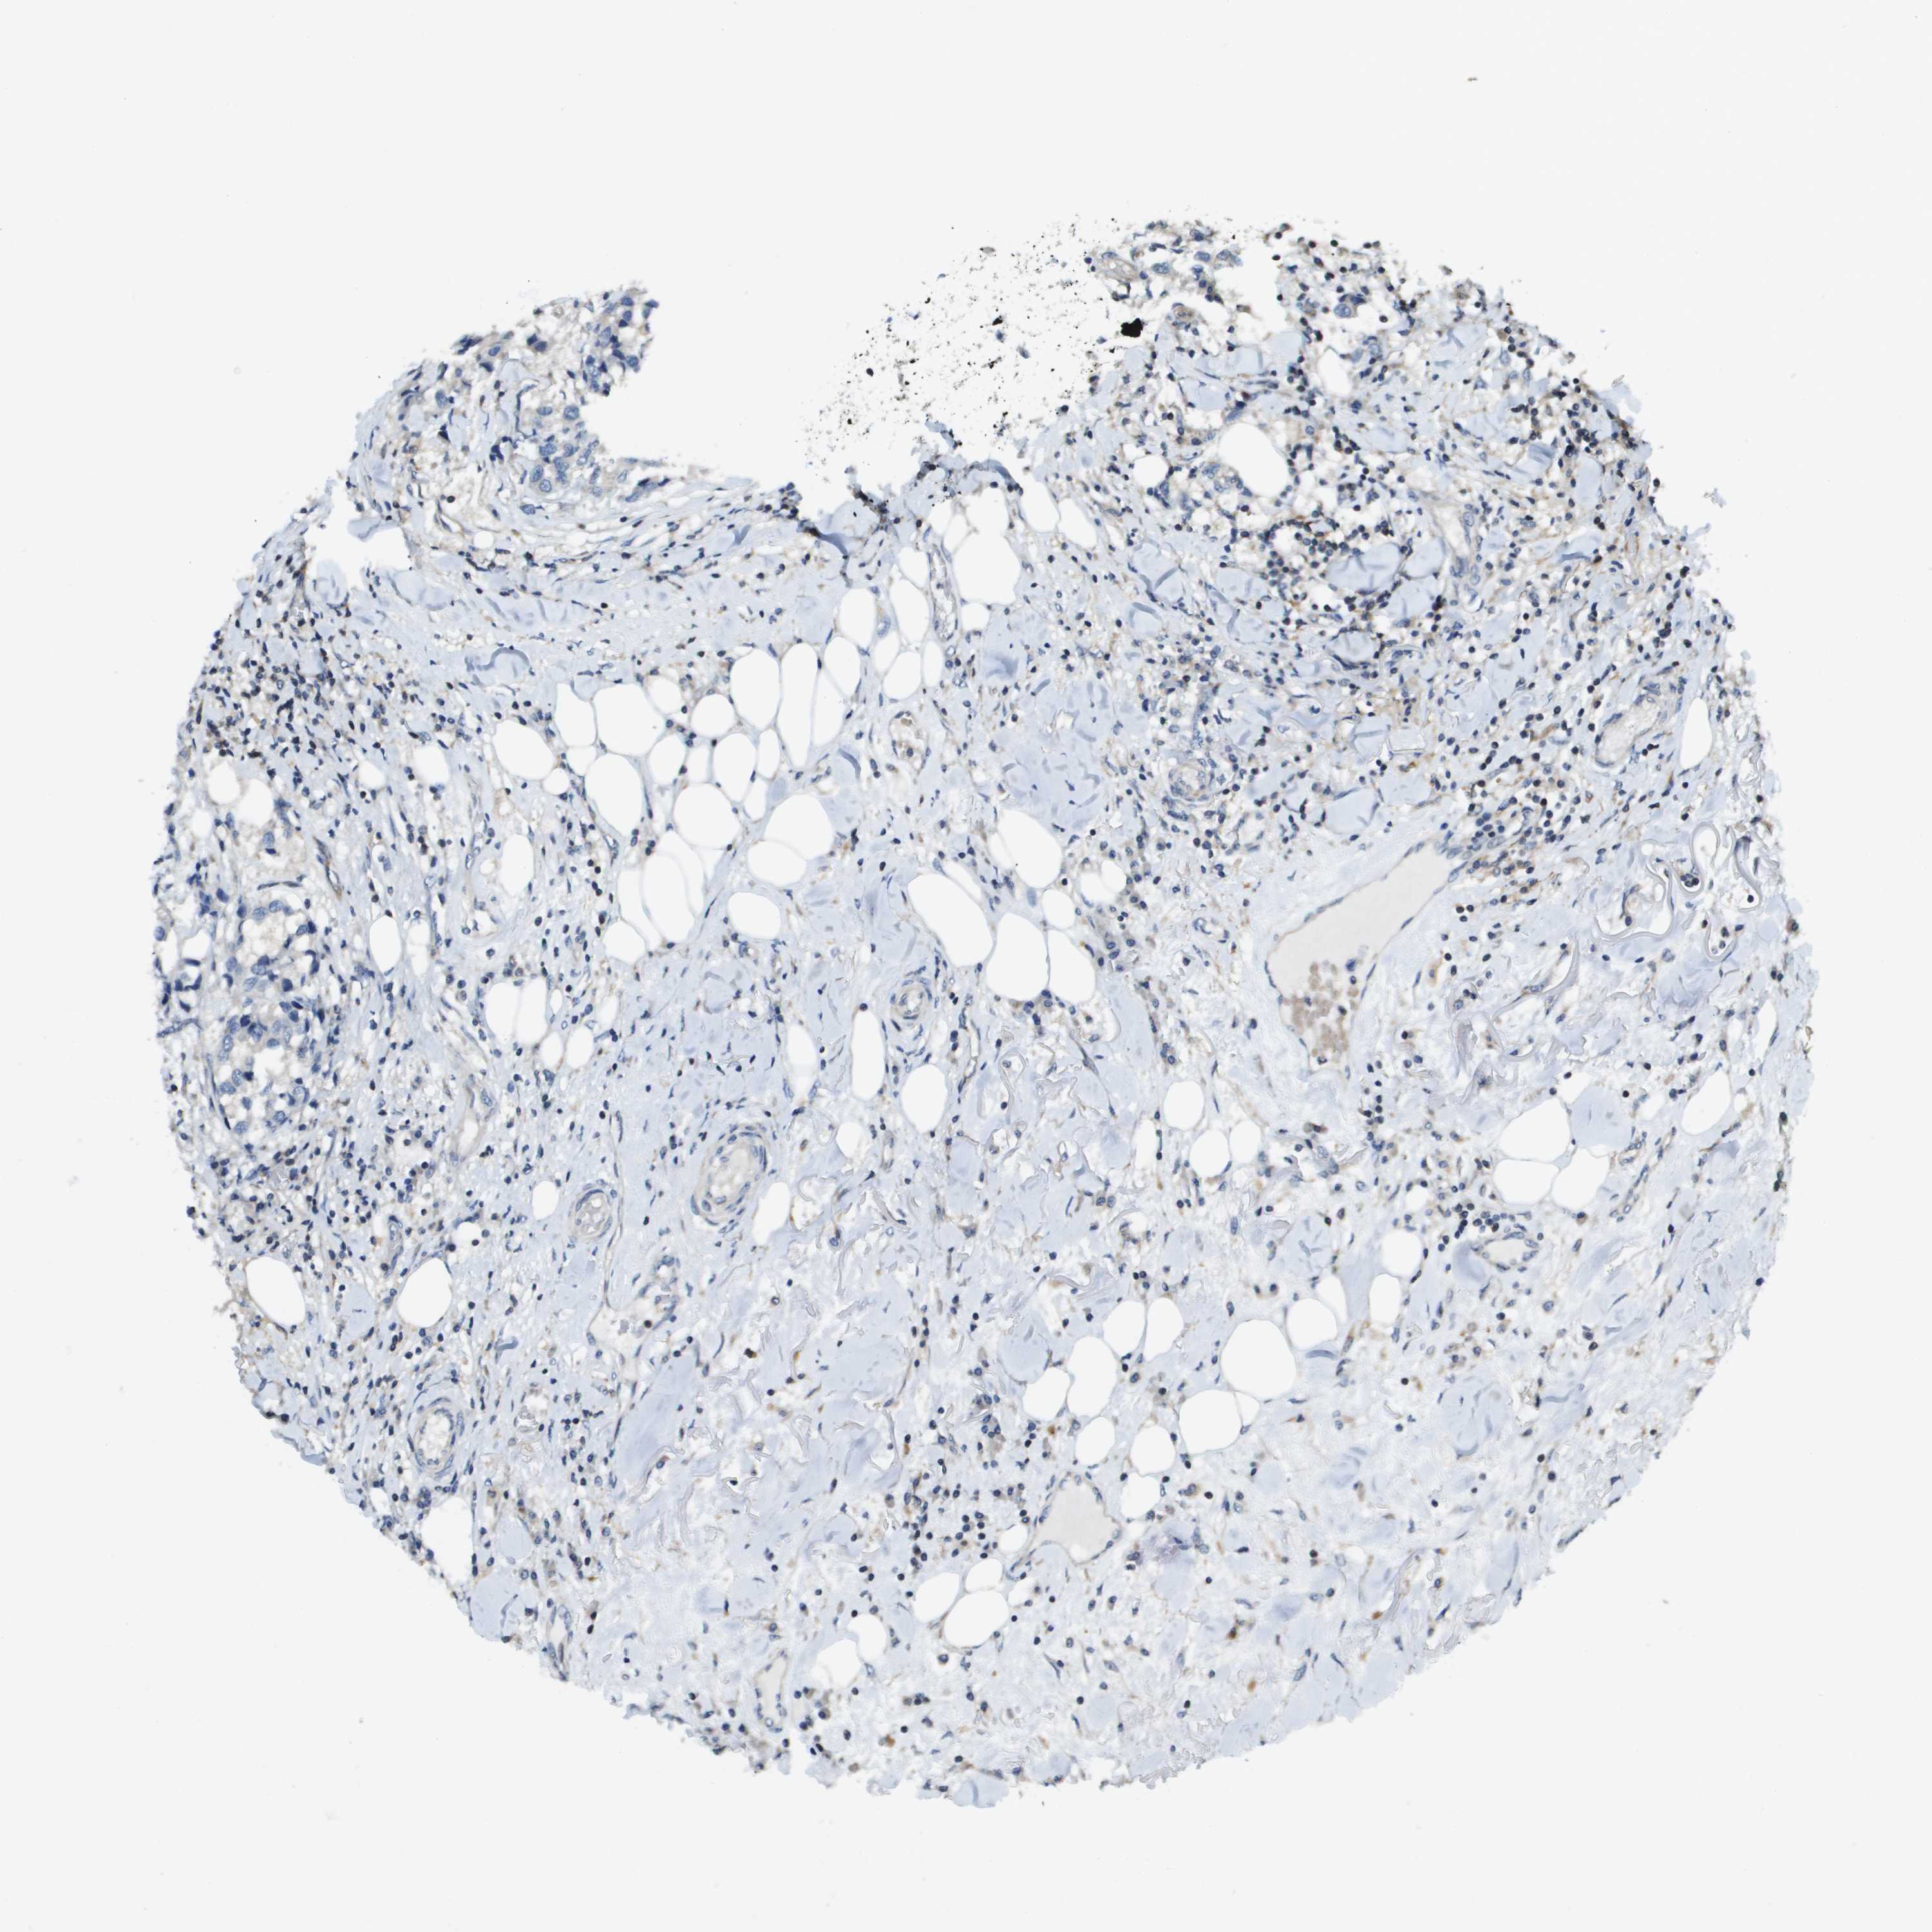

BRCA TCGA BRCA VALIDATION PROTEIN EXPRESSION

ANTIBODIES

AND

VALIDATION